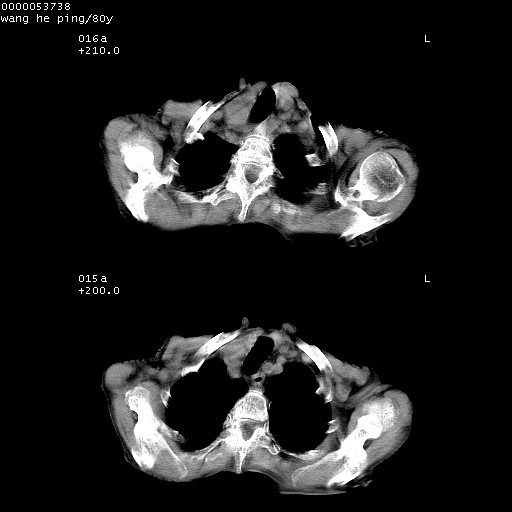

以下是引用黑白光影在2008-8-28 22:33:00的发言:[br]右肺中央型肺癌伴阻塞性肺炎,肺癌肺转移。

以下是引用lshx在2008-8-28 22:06:00的发言:[br]1.右肺中心型肺癌伴阻塞性肺炎,不除外双 肺早期转移。[br]2.心包积液。

以下是引用随光逐影在2008-8-29 7:40:00的发言:[br]1)右肺中心型肺癌伴阻塞性肺炎,肺内转移。2)心包积液(少量)。

以下是引用wqs571018在2008-8-28 21:56:00的发言:[br]右肺中心型肺癌伴阻塞性肺炎可能。

以下是引用liuyue在2008-8-28 22:46:00的发言:[br]1.右肺中心型肺癌伴阻塞性肺炎。[br]2.心包积液(少量)。